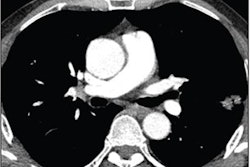

Next, they collected baseline data obtained for each patient during diagnostic clinical workup, including clinical information; contrast-enhanced chest CT scans; digitized PD-L1 immunohistochemistry slides of tissue containing NSCLC; genomic features from the MSK-IMPACT clinical next-generation sequencing platform; and their immunotherapy outcomes.

The clinical data were annotated by domain experts and then a computational workflow was developed to extract patient features. For the CT exams, radiomics features were extracted separately for lung parenchymal, pleural, and nodal lesions.